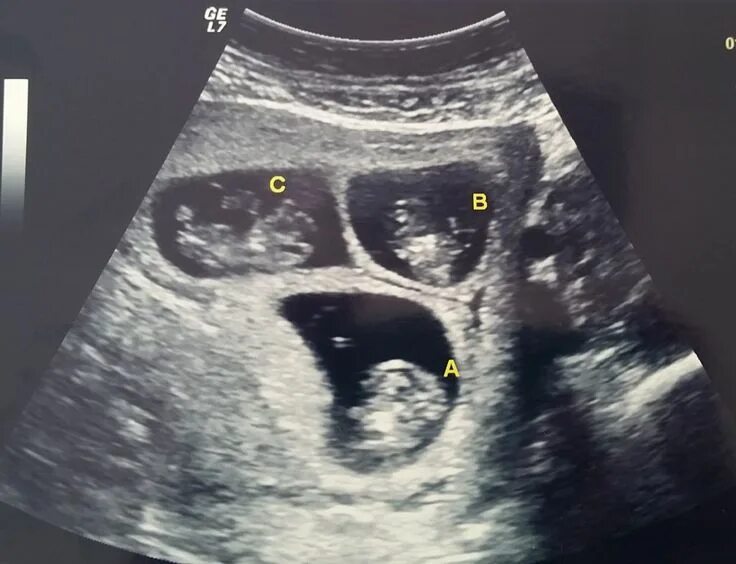

27 недель беременности двойня